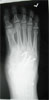

Pre Op

Old polio leg in 38year old male with 5cm shortening lower leg and equinus foot(partially correctible).Previous triple arthodesis done elsewhere many years ago

Progress

just before 2nd surgery to correct equinus(foot osteotomies)